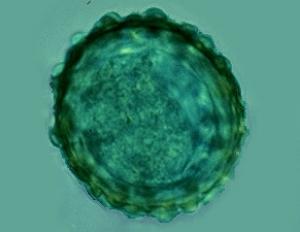

3- Ascaride : Parascaris equorum.

Photo Laboratoire Mérial

Morphologie : Adulte : Gros ver blanc de 15-50 cm X 6-8 mm. Œuf : de grande taille, 90-100 µm de diamètre, globuleux, à paroi épaisse et irrégulière, renfermant une cellule.

Localisation : Intestin grêle

Epidémiologie : Evolution chez les jeunes chevaux de la naissance à 2 ans, par ingestion d'œufs larvés très résistants dans le milieu. Migration larvaire passant par les poumons avant d'atteindre l'intestin (période prépatente de 80 jours). Pas de transmission par le lait ou in utero.

Etude clinique : Retards de croissance, troubles osseux et tendineux, entérite et colique, parfois obstruction intestinale par pelotes ascaridiennes, voire déchirure et péritonite mortelle.